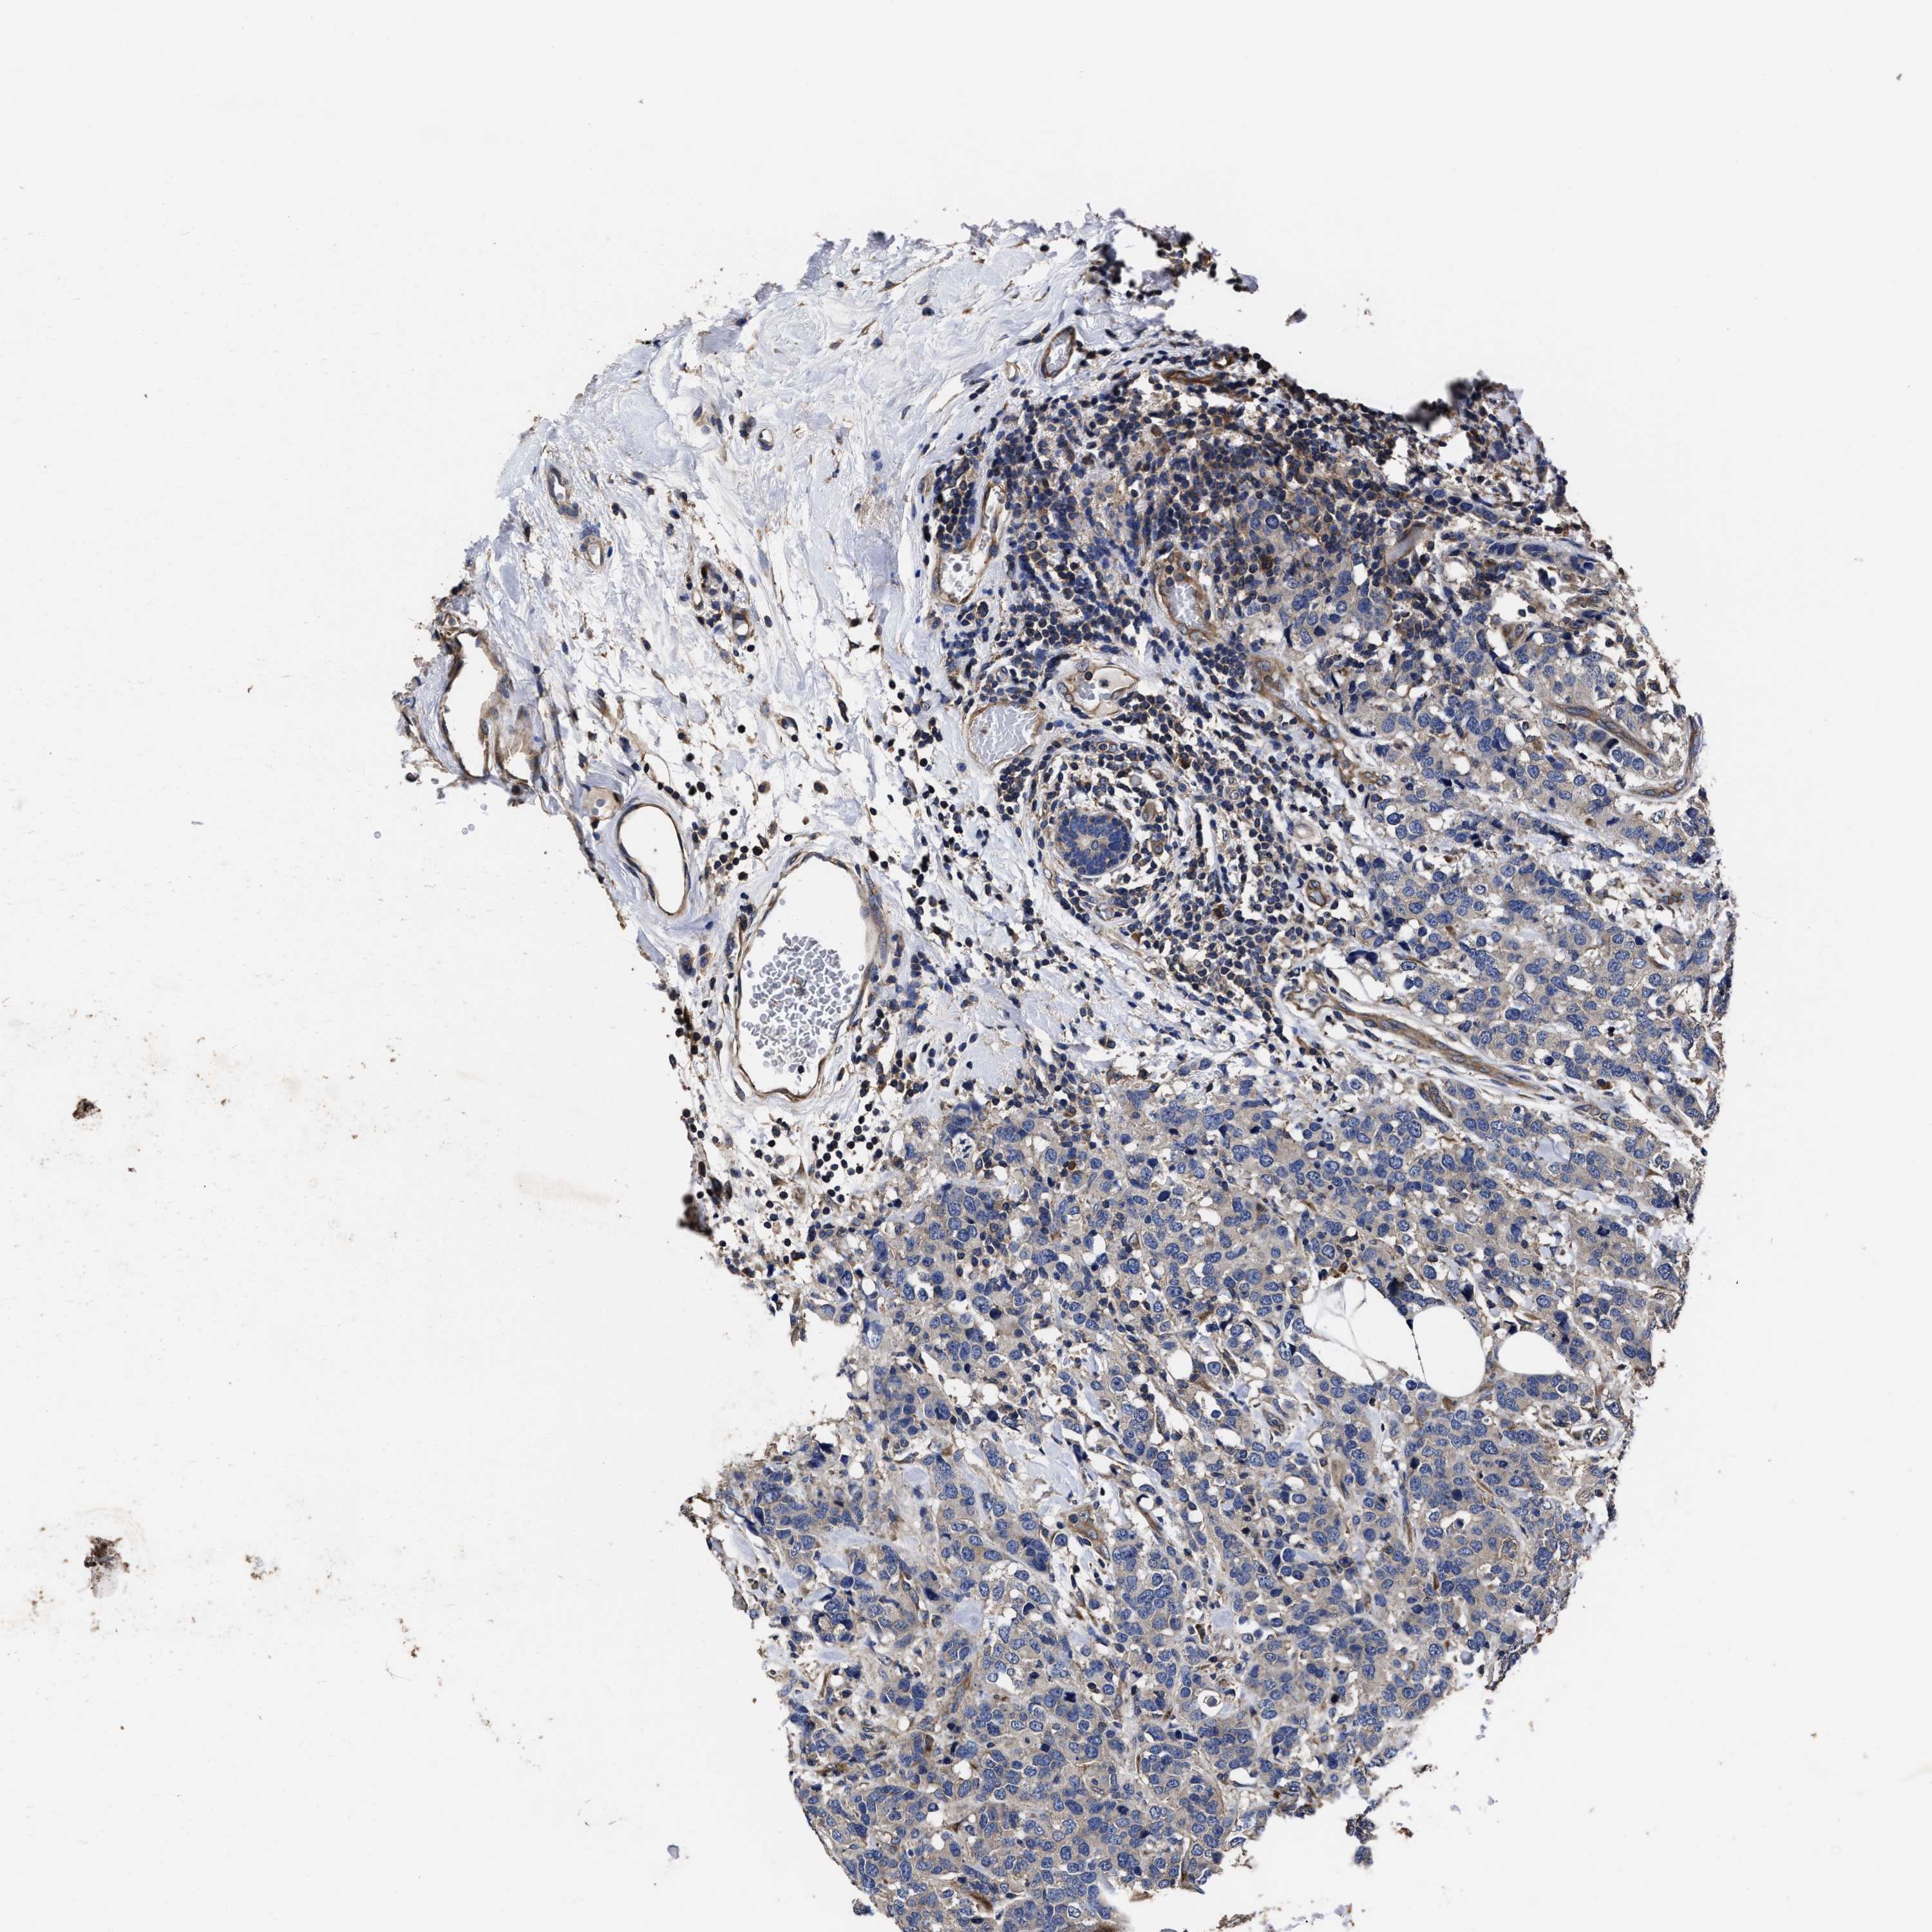

CANCER BREAST CANCER Show tissue menu

BRCA TCGA BRCA VALIDATION PROTEIN EXPRESSION